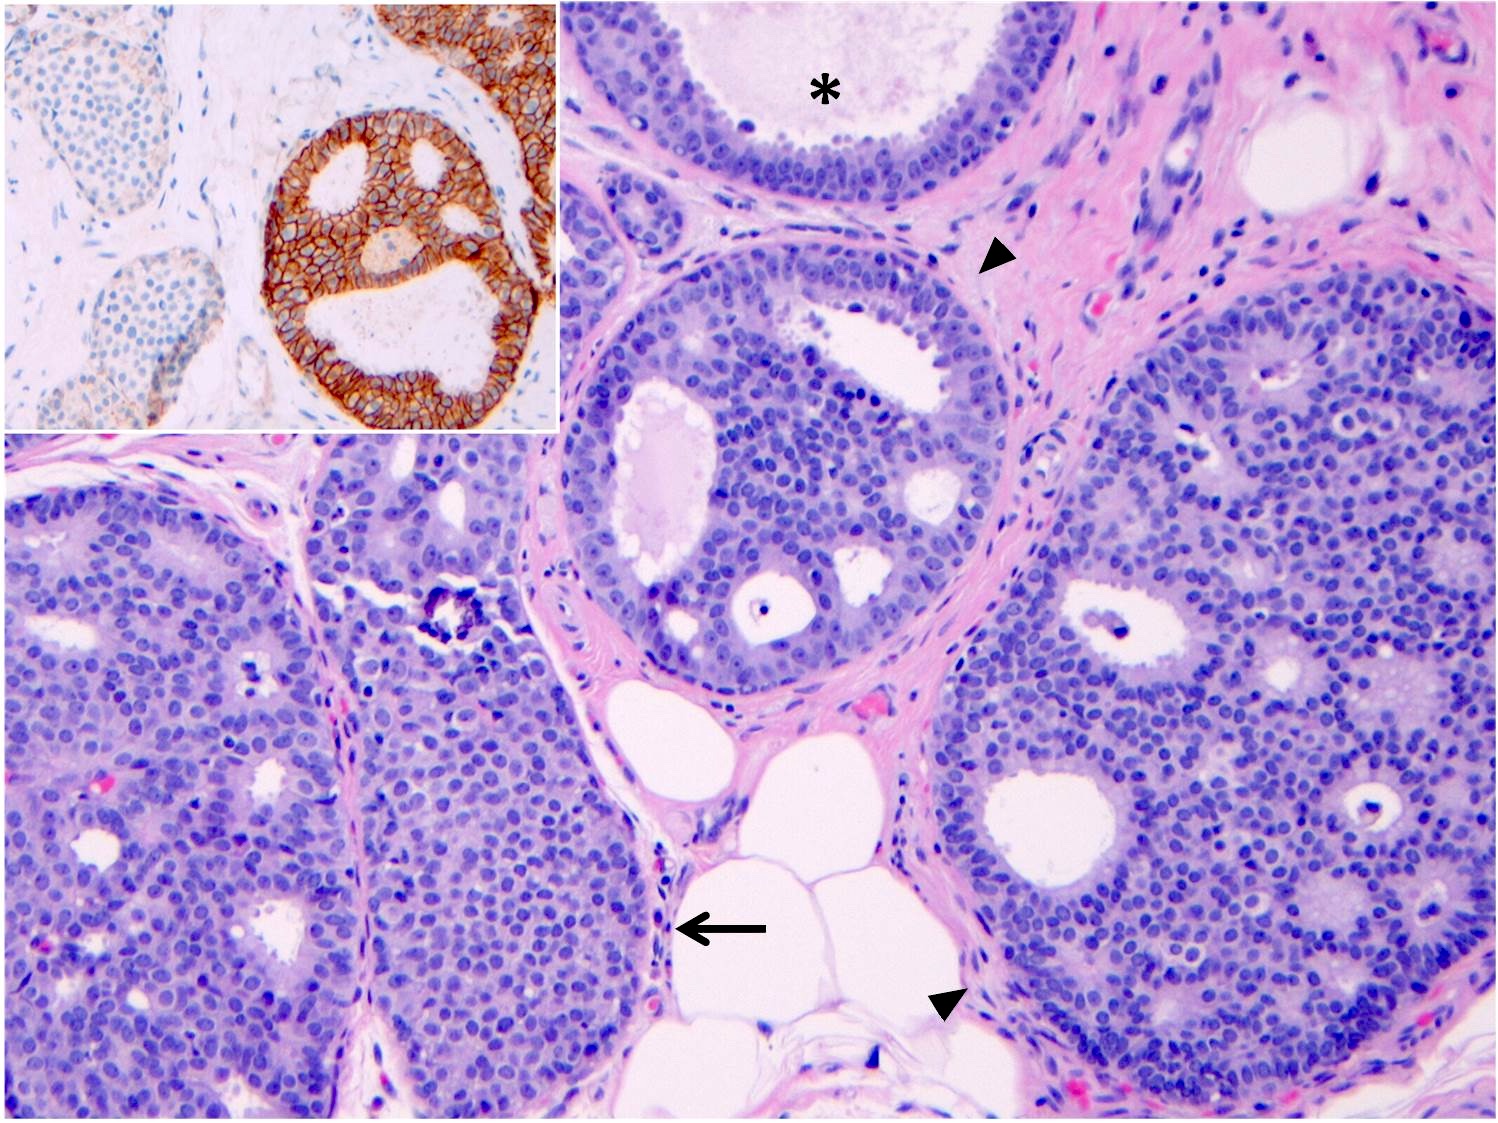

Microscopic (histologic) description

- LCIS involves the terminal duct lobular unit (TDLU), filling and distending acini

- > 50% of the acini in a TDLU must be filled and expanded to qualify as LCIS; otherwise, called atypical lobular neoplasia

- Lobular distention is defined as the presence of ≥ 8 cells in the cross sectional diameter of an acinus

- Involved lobules may be compared with uninvolved lobules to estimate the degree of distension

- ALH only partially involves the lobule by filling up the acini without significant distention

- LCIS most often involves lobules but may also grow along the basement membrane of ducts (i.e., pagetoid spread)

- Pagetoid spread in ducts is the characteristic growth of cells between luminal and myoepithelial layers of a duct without destroying ductal epithelium or filling up ductal lumina

- Often makes the ducts appear convoluted; this is called a cloverleaf pattern

- LCIS may secondarily involve (or arise in) sclerosing adenosis, radial scar, fibroadenoma, collagenous spherulosis or papilloma

- Classic LCIS cells are monomorphic, evenly spaced, loosely cohesive and do not show polarization or gland formation

- 2 types of cells are described:

- Type A: nuclei are small to slightly enlarged (1 - 1.5x size of lymphocyte) with uniform round nuclei and inconspicuous nucleoli

- Type B: nuclei larger (2x size of lymphocyte), more abundant cytoplasm and more prominent nucleoli

- Type A and B cells can coexist in the same lesion

- Cytoplasm of LCIS cells is typically pale to lightly eosinophilic with indistinct cell borders

- In almost all cases of LCIS, at least some cells contain intracytoplasmic vacuoles or lumina, which may contain an eosinophilic globule; this feature is not specific to LCIS

- Vacuoles may be subtle such that special histochemical stains for mucin are required in order to demonstrate; alternatively, they may be large enough to push the nucleus against the cell membrane and produce signet ring cell forms

- Outer layer of myoepithelial cells is retained in the acini and ducts involved but it may be attenuated

- In some cases, scattered myoepithelial cells can be admixed with the neoplastic epithelial cells within the involved spaces

Microscopic (histologic) images

Contributed by Anna Biernacka, M.D., Ph.D.